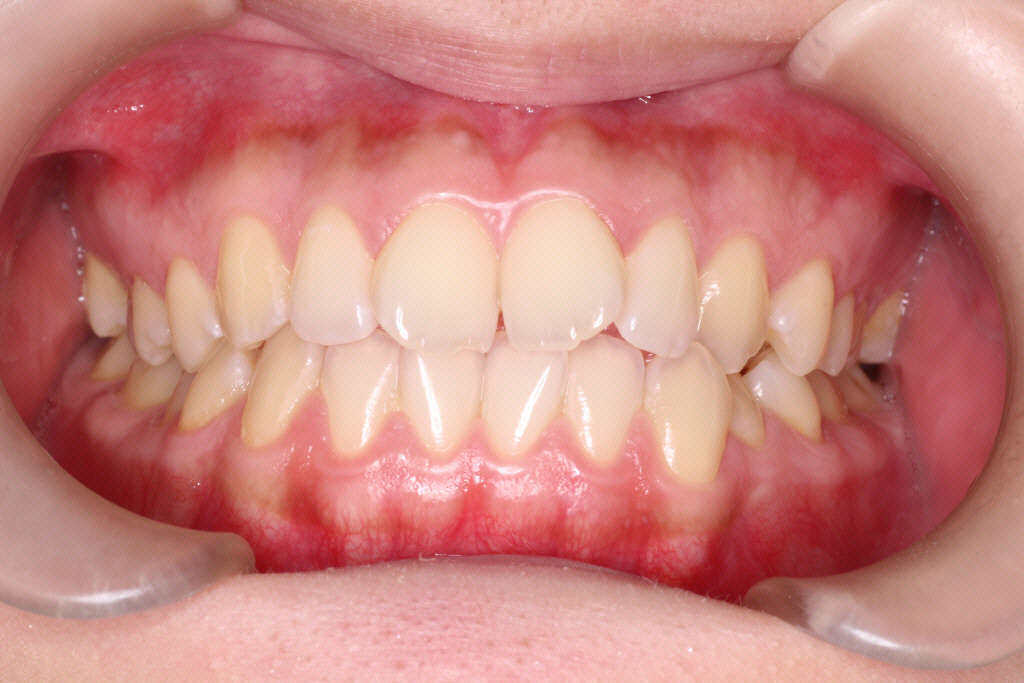

初診時の状態です。

初診時の奥歯の噛み合わせは上の歯と下の歯が1歯対1歯で噛めているので、奥歯はそのまま動かさず、

ねじれている前歯を動かしていきたいのですが、スペースがないので、そのスペースをつくらなければなりません。